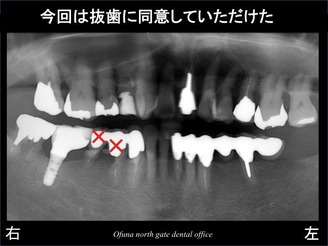

その結果、ようやく抜歯に同意していただけました。

次に問題となったのが、抜歯後の治療の進め方です。

2歯とも抜歯してしまうと 当然のことながら 欠損してしまいます。

患者様は、治療期間中に歯がないことは嫌とのことでした。

また、義歯(入れ歯)を使用することもご希望されませんでした。

とりあえず、奥の1歯のみ抜歯します。

そして、抜歯部にインプラントを埋入します。